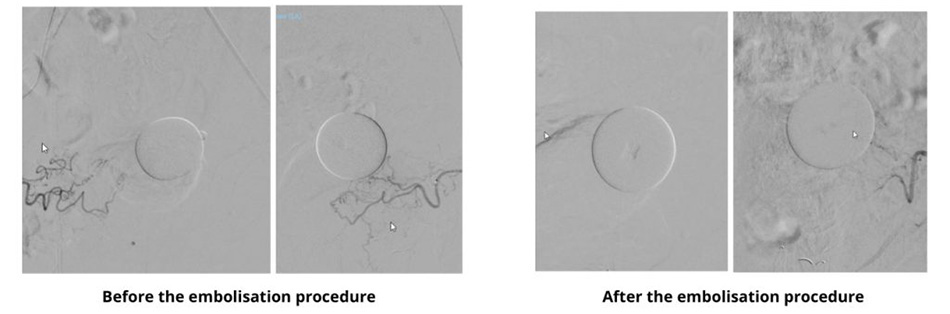

DSA images before and after the embolisation procedure. The prostate artery has been completely embolised.

Upon a recommendation, Mr H. sought medical consultation at FV Hospital. Dr Huynh Huu Danh, Specialist Level I in the Imaging & Interventional Radiology Department, diagnosed him with a significantly enlarged prostate compressing his bladder. Dr Danh proposed prostatic artery embolisation (PAE) as a treatment option. This minimally invasive procedure involves guiding a microcatheter from the femoral artery to the arteries supplying the prostate, where embolic agents are injected to block the blood flow. Over time, the prostate shrinks, alleviating pressure on the bladder and urethra, and gradually improving urinary symptoms. Mr H. agreed to undergo the procedure.